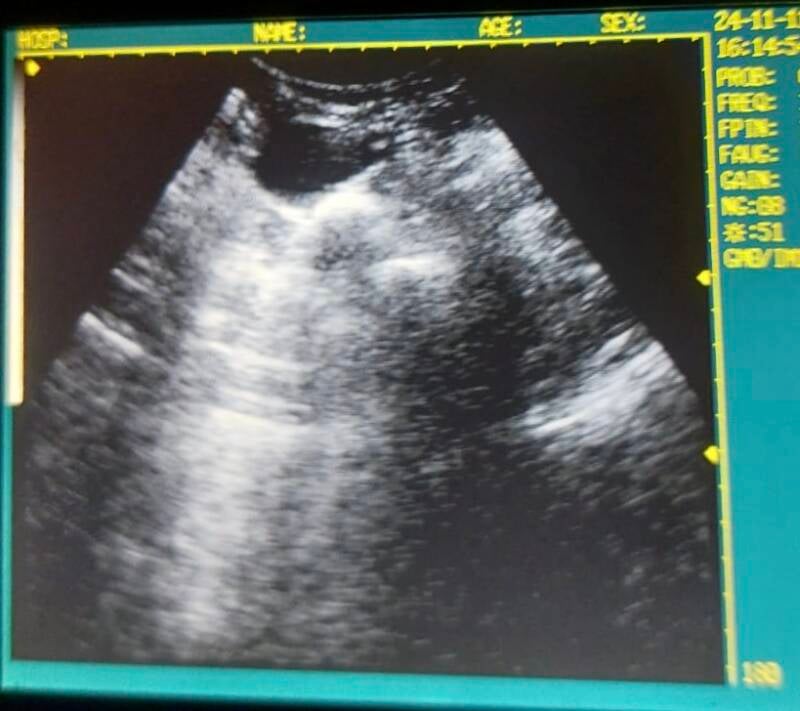

Geweldig nieuws: Merle is drachtig! Een recente echo heeft bevestigd dat meerdere puppy’s onderweg zijn, en wij staan op de wachtlijst voor een van deze kleine wondertjes. Nu is het afwachten of er een gepaste match voor ons erbij mag zijn.